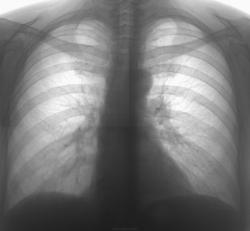

Примерно так + локальное усиление легочного рисунка, уплотнение главной междолевой плевры.

Прошу прощения, но Вы указали на корня сосуды. А то, что в прямой мы все увидали, на боковой не видно его.)